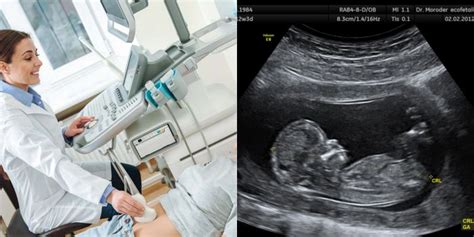

Subchorioninė hematoma (SCH) yra būklė, kai nėštumo metu kraujas kaupiasi tarp gimdos sienelės ir placentos. Nors tai gali atrodyti nerimą kelianti, daugelis moterų, sergančių SCH, turi sveiką nėštumą. Subchorioninė hematoma atsiranda, kai kraujas kaupiasi tarp choriono (išorinės membranos, supančios embrioną) ir gimdos sienelės. Ši būklė būdinga ankstyvuoju nėštumo laikotarpiu ir gali būti įvairaus dydžio. Makšties kraujavimas: Tai yra labiausiai paplitęs simptomas. Subchorioninės hematomos paprastai diagnozuojamos ultragarsu. Procedūra padeda sveikatos priežiūros paslaugų teikėjui įvertinti dydį, vietą ir galimą riziką, susijusią su hematoma.